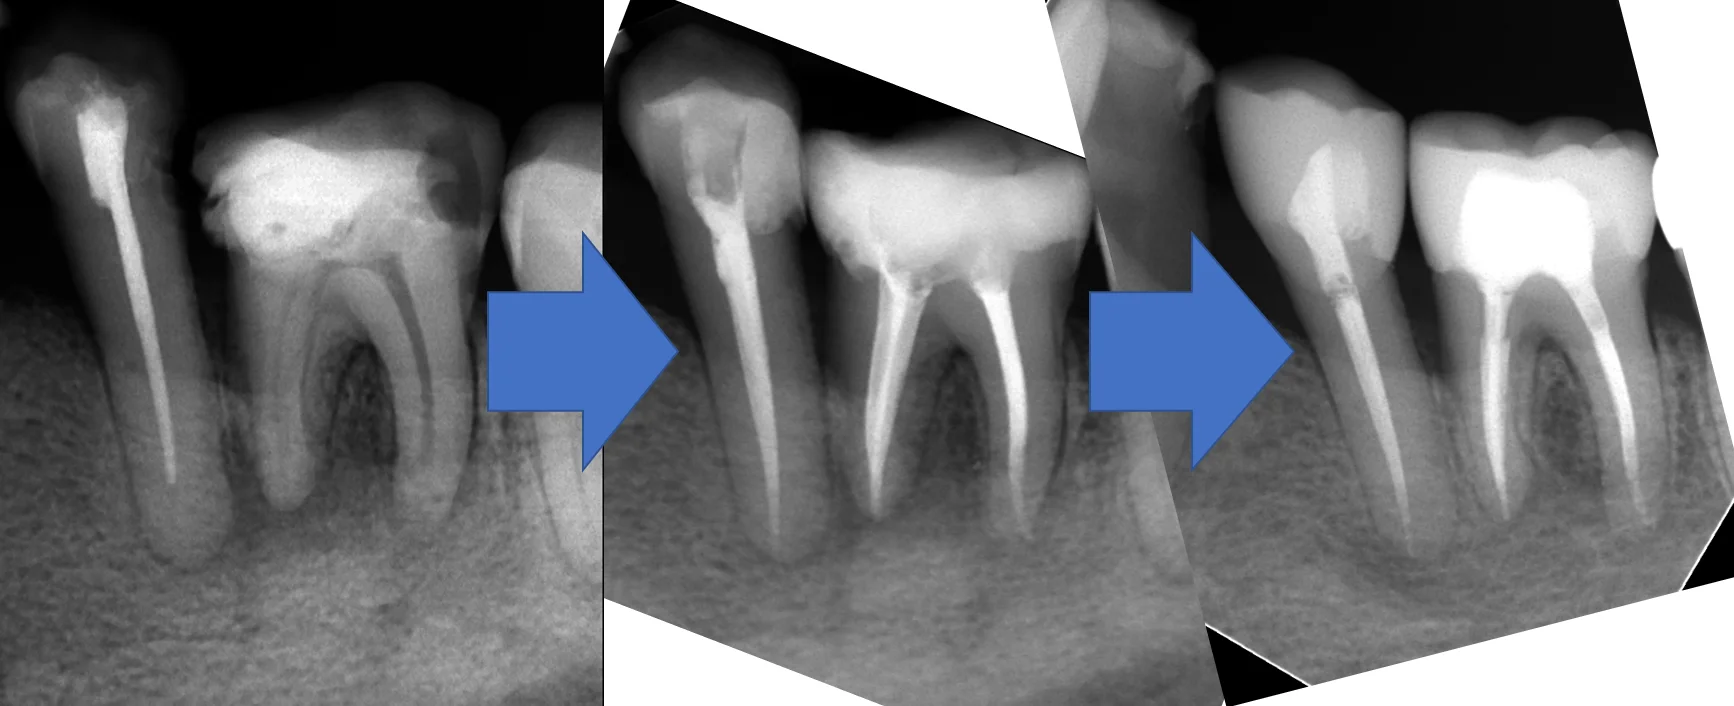

で、いつも通り、隔壁を作り・・・1回神経の治療を行った所、どちらの歯も叩いた時の症状が消えた為、神経の治療を完了させました。その際のレントゲンがこちらです。

骨が溶かされた部分はこういう感じで黒く見えてくるんですが・・・

基本的に数年単位で骨が溶かされてくるので、骨が出来るのも数年単位になってきます。

骨代謝の激しい若年者であれば1月や2月で大きく変わってくることはありますが、通常は半年くらい経過してみないことには本当に治療が上手くいったかどうかは分かりません。

今回は治療開始から治療完了までが1ヵ月半という短い期間だったにも関わらず比較的骨が出来てきているのが分かりますね。

そしてその後、1年経過時点でメンテナンスで来院された際に再度レントゲンを撮らせて頂きました。

ほとんど完全に黒い部分が消えてくれているのが分かるかと思います。

治療終了後はセラミックを希望されたので、通法に則って形作り・型取りを行い、Setしました。

レントゲンを見る限りだと適合は非常に良いですね。

術前・術後・術後1年で並べるとこんな感じです。